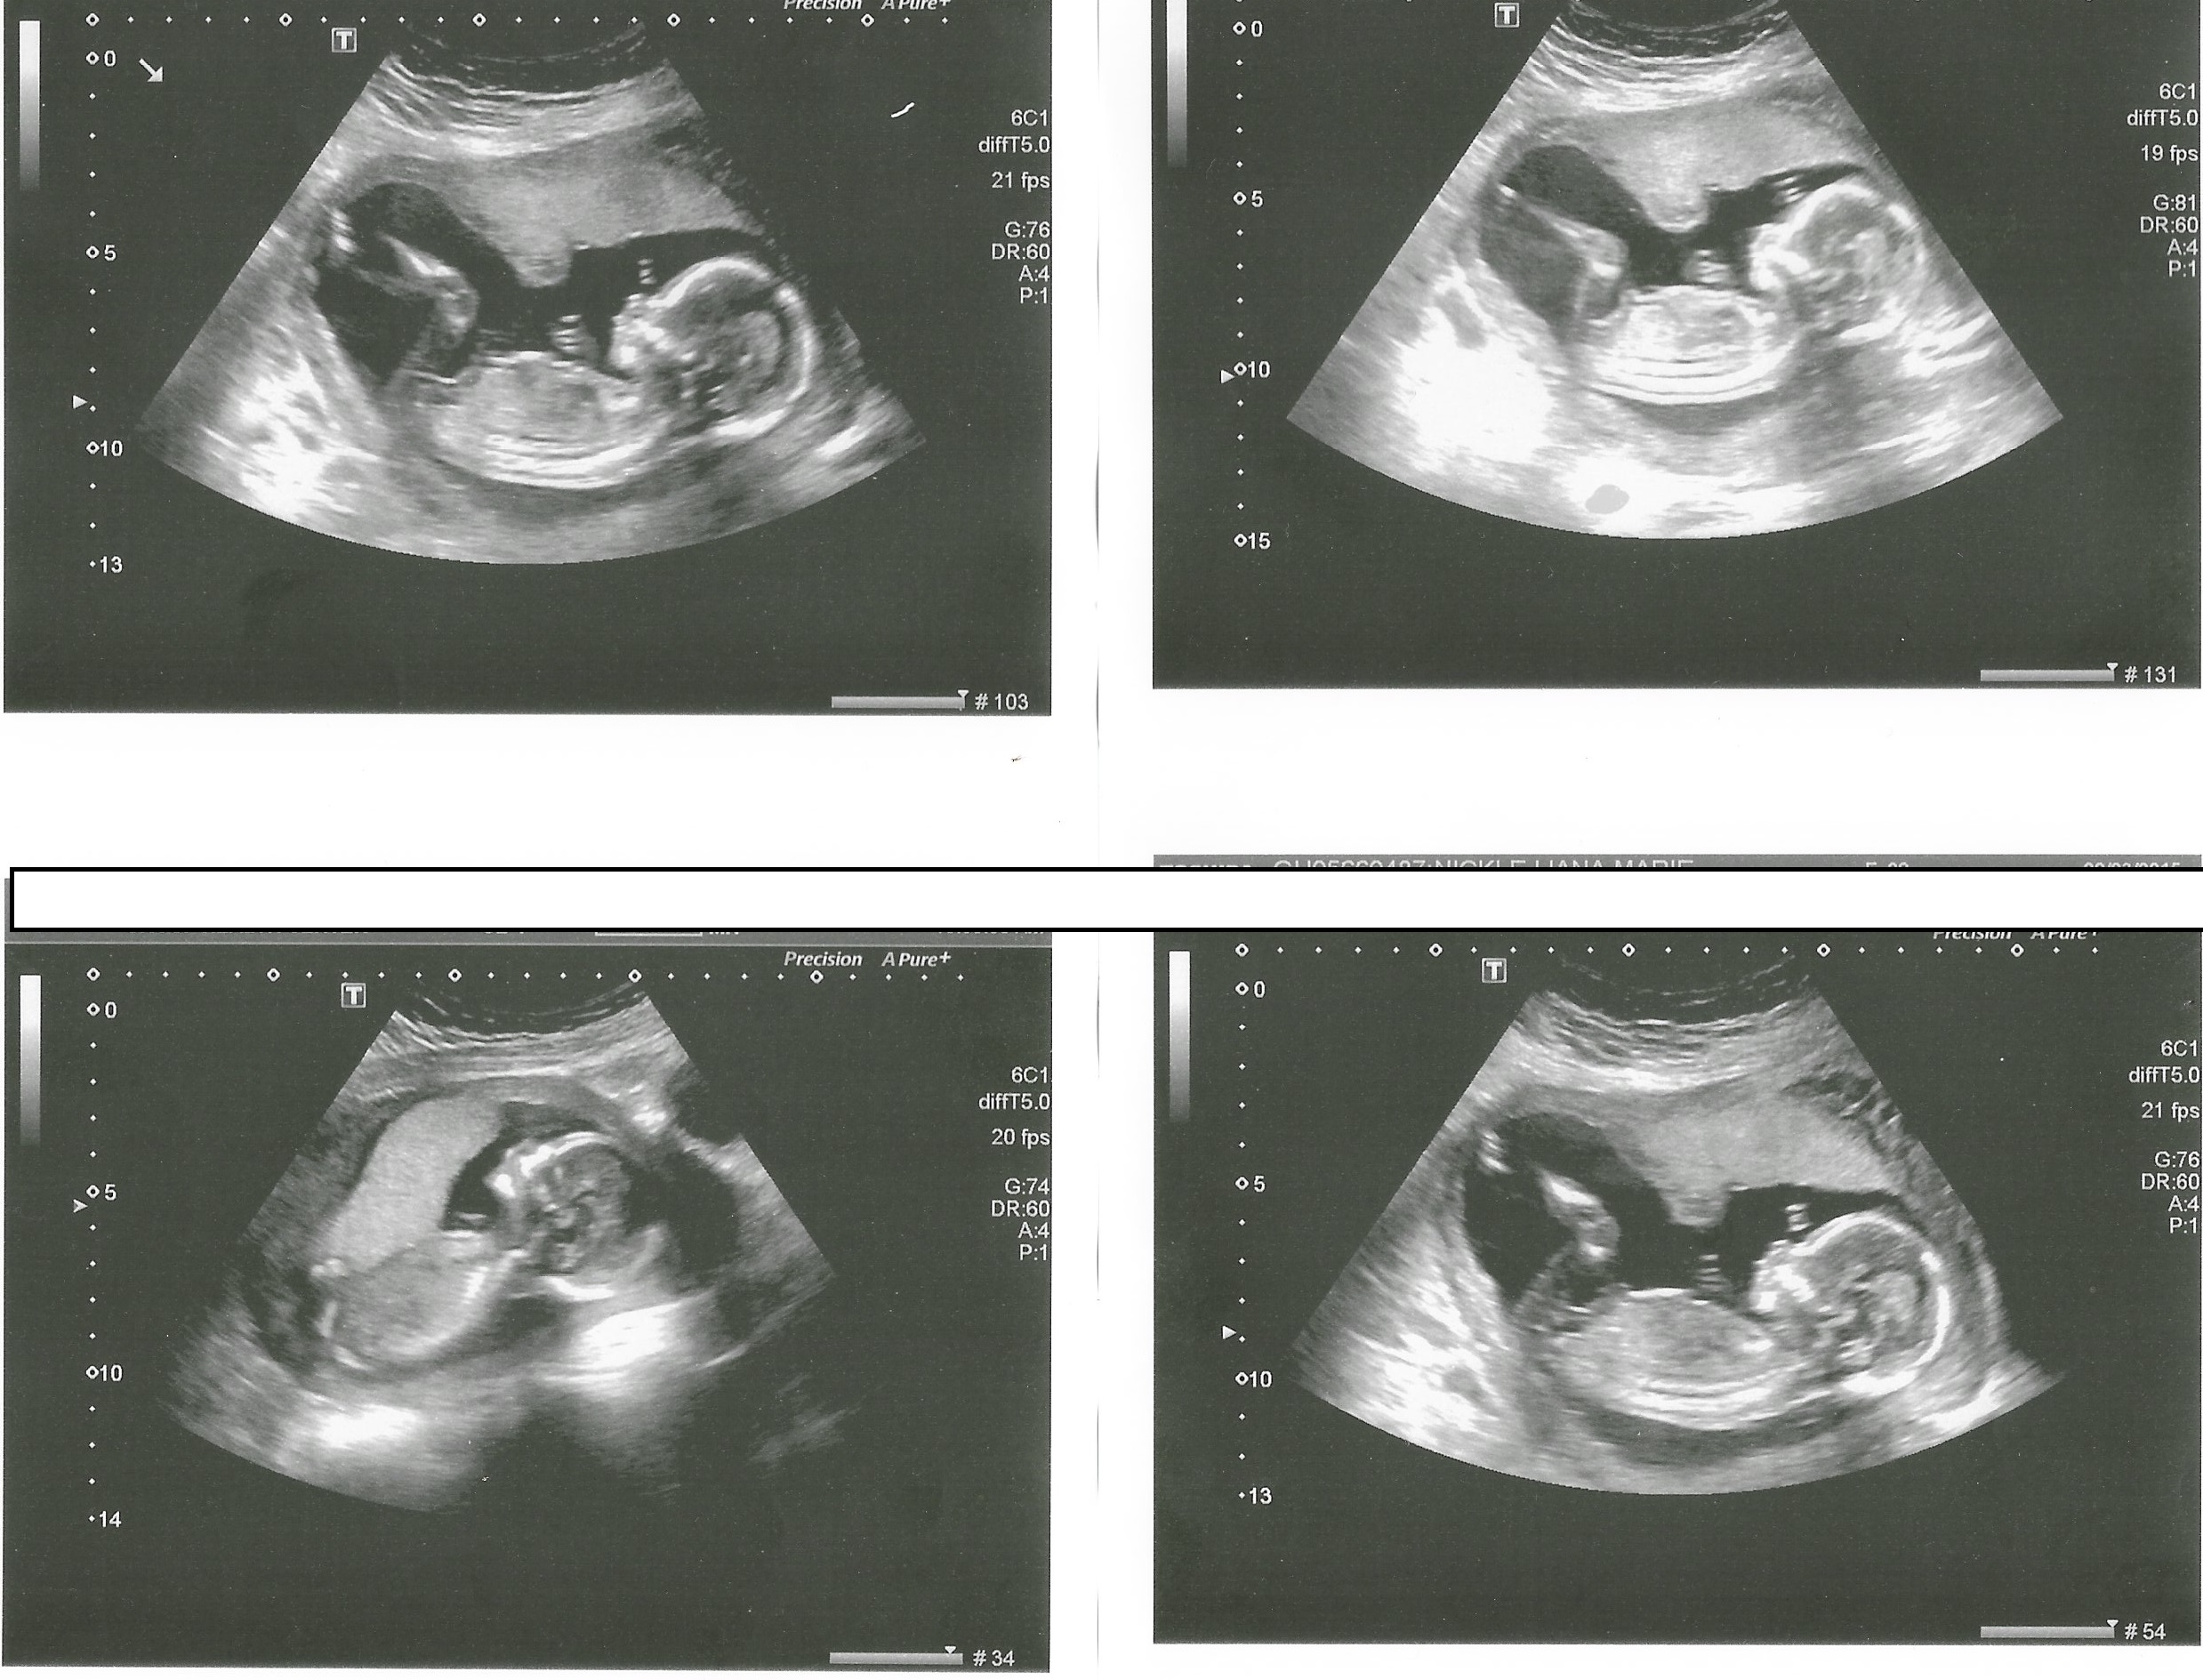

We got new pictures at 16w5d! My husband wasn't with me, so I didn't ask about gender, but I'd love guesses if the pics have any new clues. :)

Attachment 24353